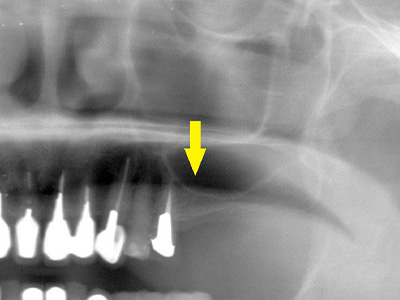

そこで、左側はソケットリフトを併用して行いました。

インプラント埋入手術後のCT、黄色の矢印部分、インプラント周囲にドーム状に補填材が白く写り、インプラントがしっかりと埋入できています。